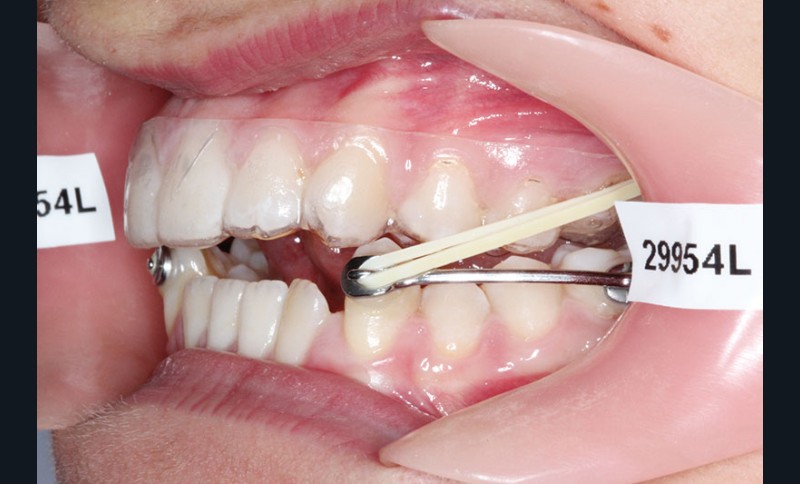

1re phase : recul des secteurs latéraux mandibulaires avec le Motion Classe III Carriere (fig. 4 à 6)

Nous mettons en place des bras latéraux Motion associés à des élastiques intermaxillaires ancrés sur des brackets sur 17 et 27 et une gouttière thermoformée maxillaire portée jour et nuit :

• 1er mois : élastiques 6 oz. 1/4”

• 2e mois et suivants : élastiques 6 oz.1/4“

L’objectif de cette étape est d’obtenir un recul des secteurs latéraux mandibulaires afin de positionner les molaires et canines en classe I et de réorienter le plan d’occlusion en haut en avant.